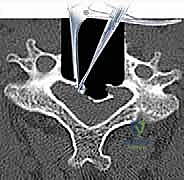

- التصوير بالرنين المغناطيسي (MRI): المعيار الذهبي لرؤية الحبل الشوكي، الأعصاب، والأقراص الغضروفية بوضوح تام، وتحديد مناطق الانضغاط.

- التصوير المقطعي المحوسب (CT Scan): ضروري جداً لتقييم البنية العظمية، التكلسات (مثل OPLL)، والكسور بدقة ثلاثية الأبعاد.

الخطوة 3: استئصال الأقراص الغضروفية وجسم الفقرة (Corpectomy)

باستخدام الميكروسكوب الجراحي وأدوات دقيقة جداً، يتم أولاً إزالة الأقراص الغضروفية أعلى وأسفل الفقرة المستهدفة. بعد ذلك، يتم استئصال جسم الفقرة العظمي المتضرر بعناية فائقة لفتح مساحة واسعة وتحرير الحبل الشوكي المضغوط.

الخطوة 5: التثبيت بالشريحة والمسامير

لضمان ثبات الدعامة ومنع حركتها حتى يكتمل الالتحام العظمي (الذي يستغرق عدة أشهر)، يتم تثبيت شريحة معدنية من التيتانيوم على الجزء الأمامي من الفقرات السليمة (التي تقع أعلى وأسفل الدعامة) باستخدام مسامير طبية خاصة.